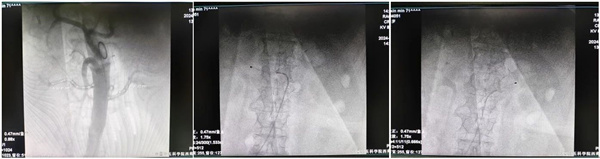

71歲的阿姨是個有著35年高血壓病史的老病友,既往最高血壓達260/180mmHg,數十年來輾轉多地求醫(yī),期間聯(lián)合使用多種不同作用機制的降壓藥物,并于當地醫(yī)院行右側腎上腺瘤切除術,血壓仍難以控制,導致其與家屬疲憊不堪,也給阿姨帶來了嚴重的降壓隱患。患者慕名來到中國中醫(yī)科學院西苑醫(yī)院,趙福海主任在充分了解患者病情的基礎上,予以患者聯(lián)合多種降壓藥物足量、足療程治療,但其動態(tài)血壓均值仍在155/64mmhg。阿姨激動地說“我這輩子血壓就降不下來了嗎?我到底該怎么辦?”面對難治性高血壓的血壓達標問題,趙福海主任帶領的介入團隊決定采用RDN為阿姨解決血壓難題。手術對左側腎動脈的4個靶點和右側腎動脈的3個靶點進行了射頻消融。手術用時約120分鐘,患者術后血壓平穩(wěn)(117/61mmHg),安返病房。